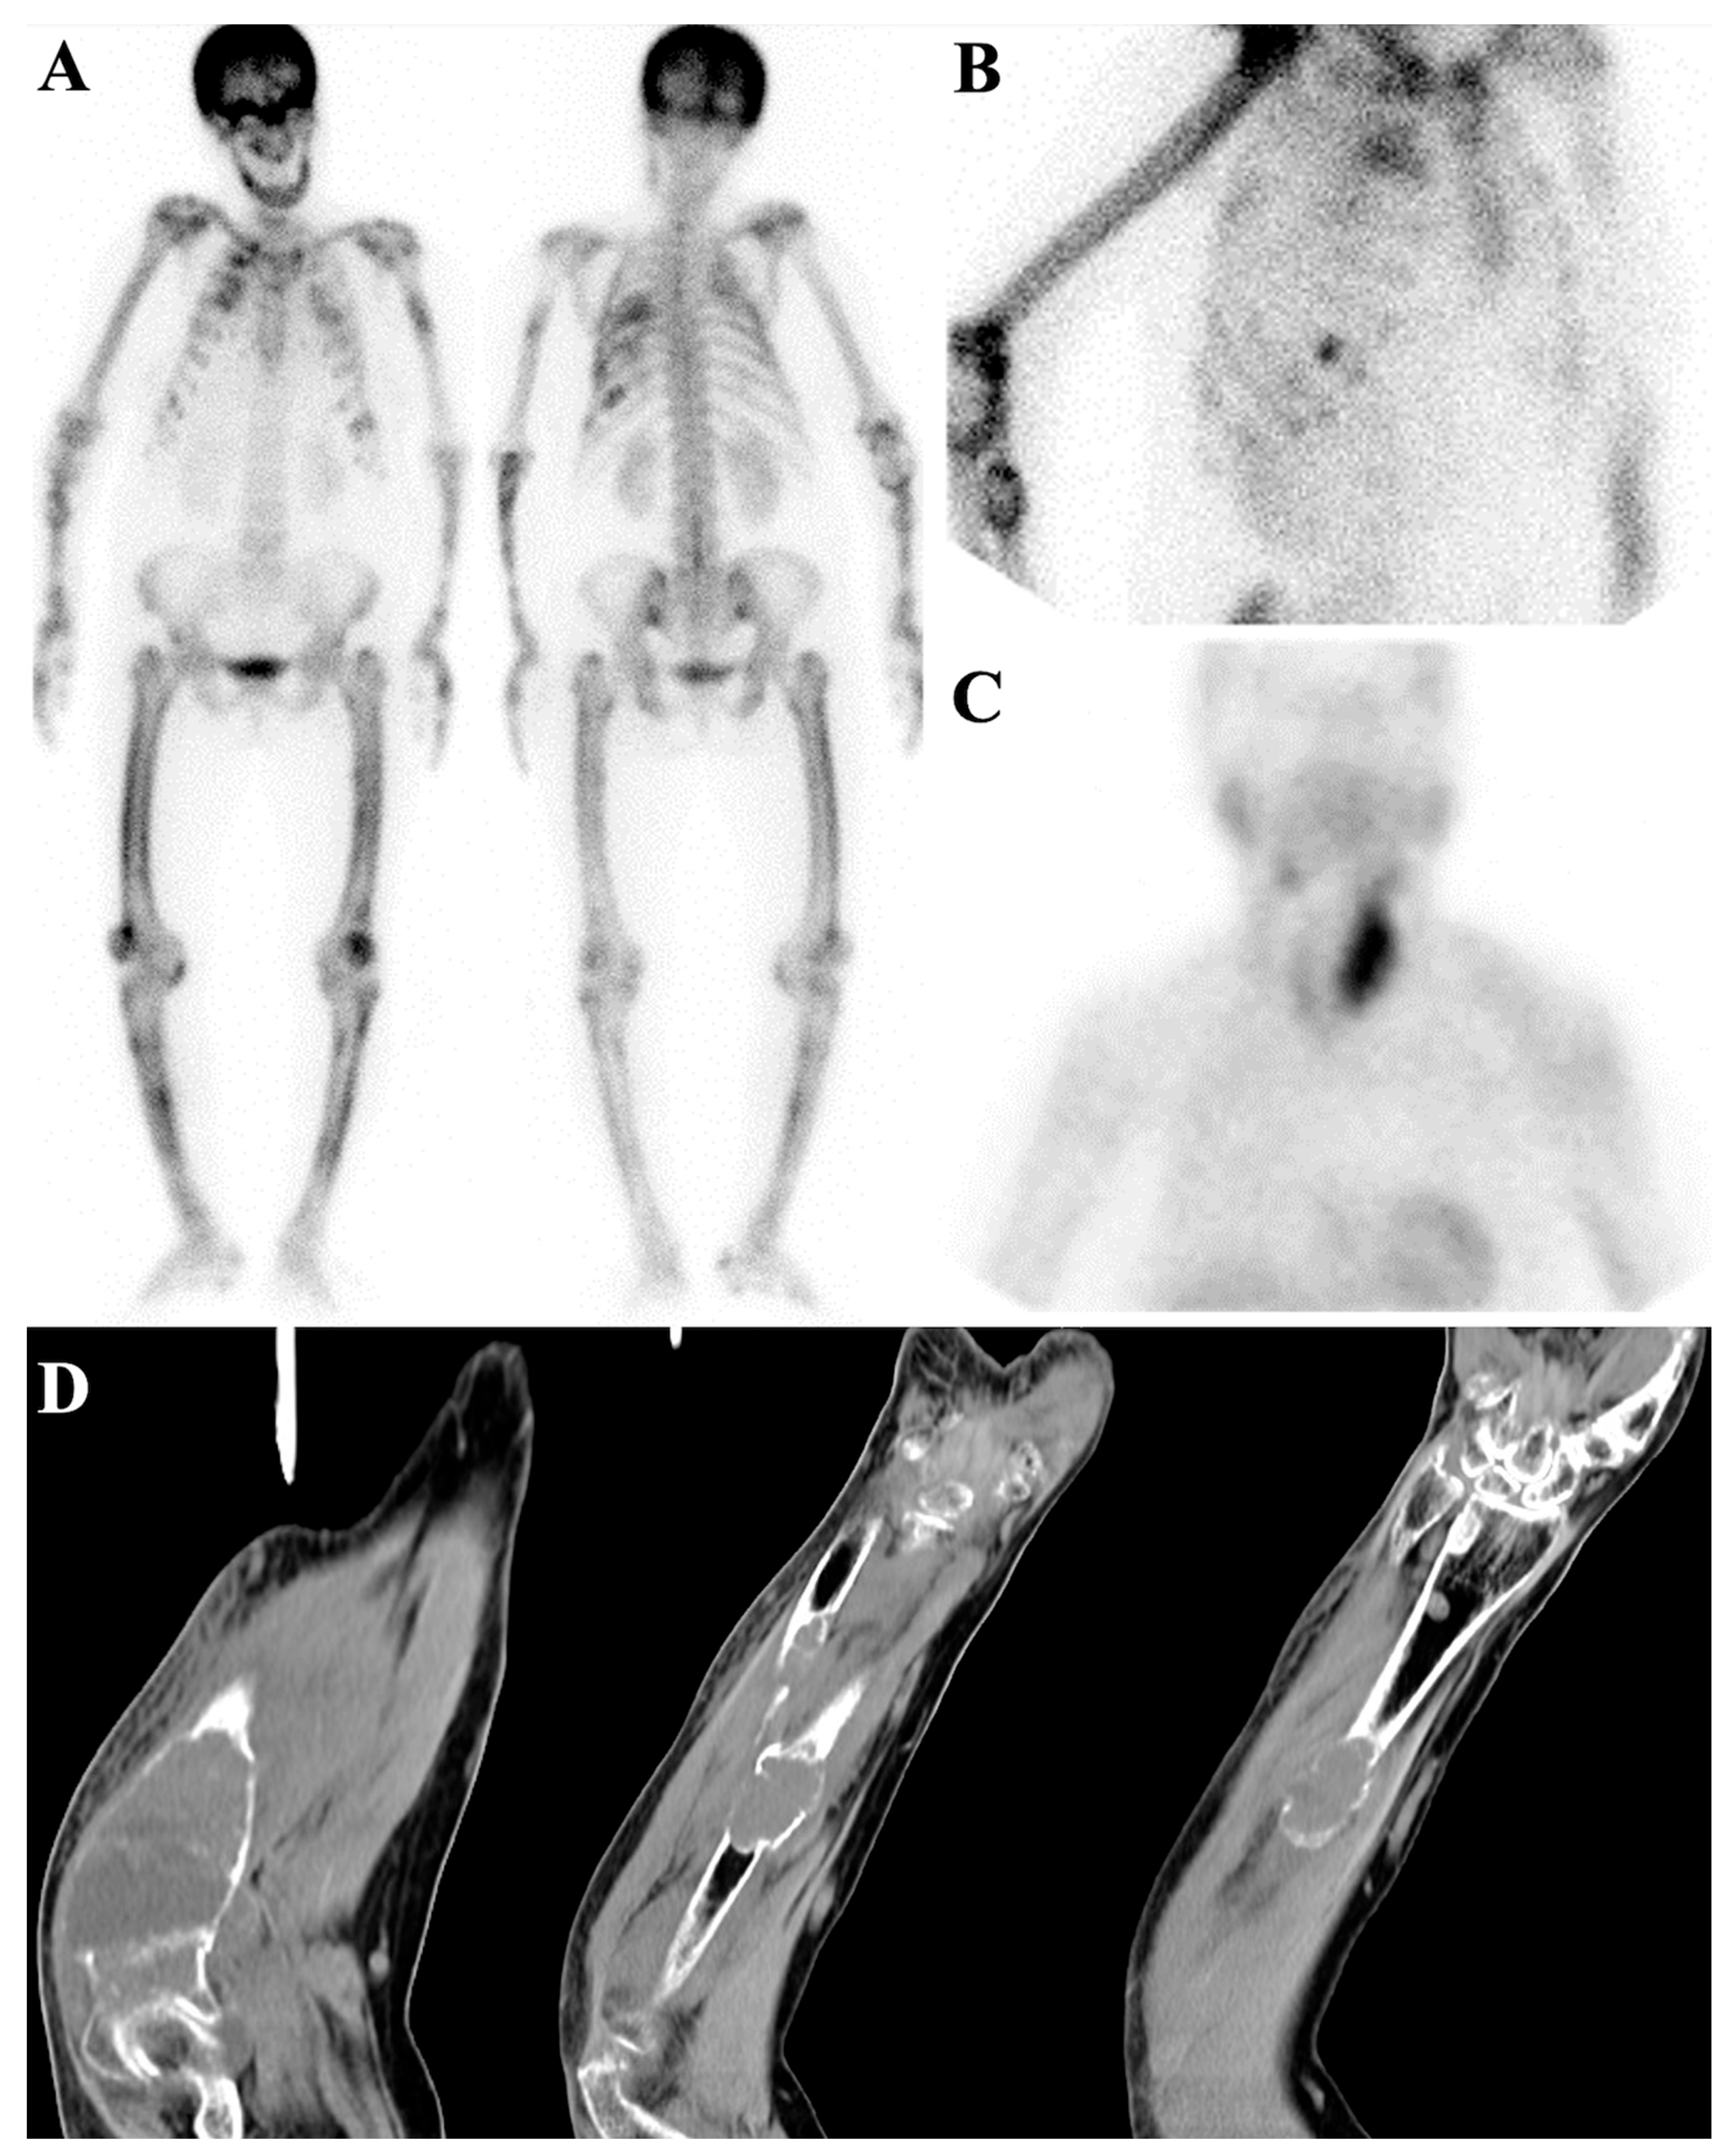

7.1. Metastatic Superscan

7.2. Metabolic Superscan

7.3. Distinguishing Metabolic Superscan from Metastatic Superscan